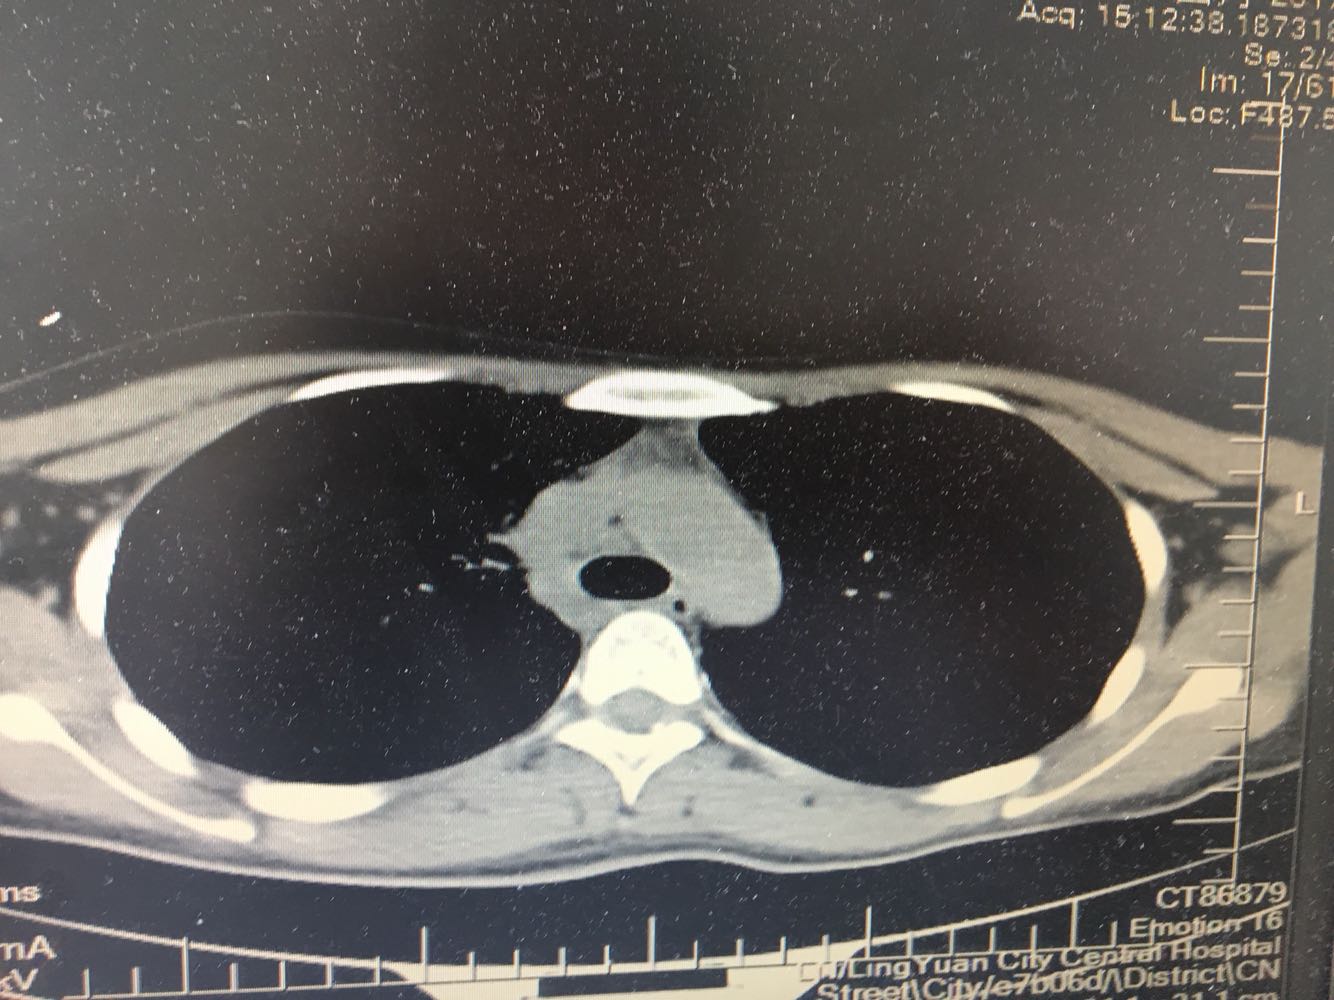

女,26岁,咳嗽1周,咳痰不畅,咽喉痒,口服阿莫西林无好转,昨日发热,体温38.5摄氏度,于门诊查肺CT后以肺炎收入院,病来无盗汗,无咳血,无消瘦及乏力,无头痛,无肢体酸痛,饮食睡眠可,二便正常

支原体肺炎?肺结核?

支原体抗体1:160,结核抗体弱阳性。支原体肺炎个别可见上叶病变,该患无结核中毒症状,考虑支原体肺炎可能性大,但肺尖为结核好发部位,需要抗炎治疗后复查观察疗效。